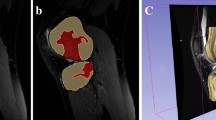

Bone model creation and coordinate system embedding

Computed tomography (CT) (SOMATOM Definition, Siemens AG, Erlangen, Germany) of all knees was performed to create a 3D bone model. CT was performed with a 0.5-mm slice pitch spanning approximately 150 mm above and below the knee joint line. Then, 3D bone models of the femur and tibia were created from the CT images using 3D-Doctor (Able Software Corp., Lexington, MA, USA). The coordinate system for 3D bone models was 3D-Aligner (GLAB Corp., Higashi-Hiroshima, Japan).

The medial condyle and the lateral condyle of the femur were considered as one cylinder [17]. The central axis of the cylinder was set as the Z-axis of the femur. The origin was the midpoint of the central axis of the cylinder that penetrates between the medial and lateral bony surfaces of the femur. A plane through the origin perpendicular to the central axis was defined as the sagittal plane. The X and Y axes of the femur were set on this plane. The line passing through the origin of the femur and parallel to the central line of the projected femoral shaft to the sagittal plane was the Y-axis. The line passing through the origin and perpendicular to the Z and Y axes was defined as the X-axis (Fig. 1).

The tangent was set posterior to the tibial condyle at the top level of the head of the fibula (Fig. 2, line 1). The tangents fitted onto the medial and lateral tibia perpendicular to the posterior tangent (Fig. 2, lines 2 and 3) and the anterior tangent (Fig. 2, line 4) were set to create a rectangle. The rectangle made from lines 1 to 4 was then translated to the tibial plateau. The midpoint of the rectangle was set as the origin of the tibia. The AP line of the bisector of the rectangle was set as the X-axis of the tibia, and the transverse bisector line of the rectangle and perpendicular to the X-axis was set as the Z-axis of the tibia. A line passing through the origin and perpendicular to the X-Z plane was set as the Y-axis of the tibia (Fig. 2).

Coordinate system of the tibia. The tangent is set behind the tibial condyle (line 1) at the top level of the head of the fibula, and it is fitted onto the medial and lateral tangents perpendicular to the posterior tangent (lines 2 and 3), and the anterior tangent is set to create a rectangle (line 4). Z-axis: transverse bisector line of the rectangle. X-axis: anteroposterior bisector line of the rectangle. Y-axis: vertical line to the X-Z plane